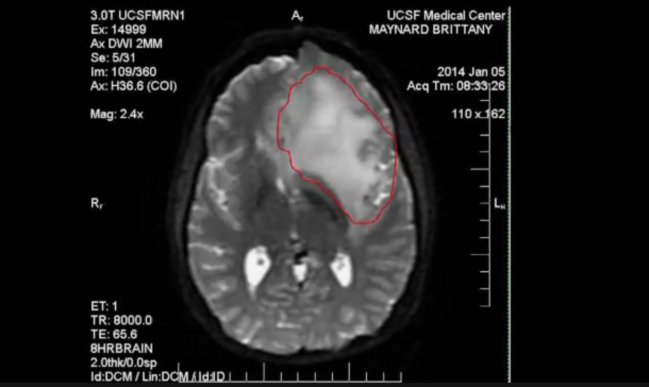

Imagen foto_00000001

Imagen foto_00000014

La joven padece de un cáncer cerebral sin cura.